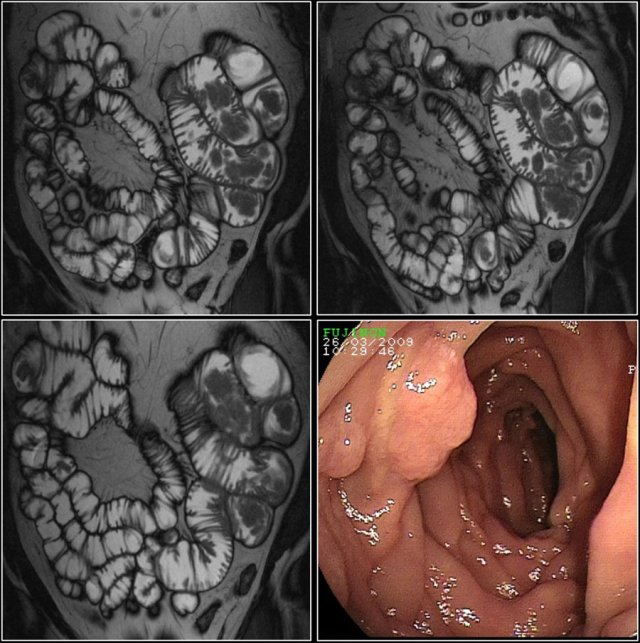

Here a patient with Peutz-Jeghers syndrome with multiple small bowel polyps, mainly located in jejunum.

Polyposis syndromes

Intestinal polyposis syndromes can be divided into the broad categories of familial adenomatous polyposis (like Gardner syndrome), hamartomatous polyposis syndromes (like Peutz-Jeghers syndrome) and other rare polyposis syndromes.

Patients with these syndromes often have multiple small bowel polyps.

Larger polyps can become malignant and can mimic primary small bowel neoplasms.

Here a patient with Peutz-Jeghers, who has multiple polyps in the jejunum.

The largest polyp in this patient was removed endoscopically.

Lipomas

These are well-circumscribed intraluminal masses with fat attenuation.

Liposarcoma of the small bowel is extremely rare.

CT shows a lesion with fat attenuation at duodenal-jejunal junction.

Low signal intensity of the mass on MR T2 fatsat (right lower image).

Endoscopic view of lipoma (right upper image).